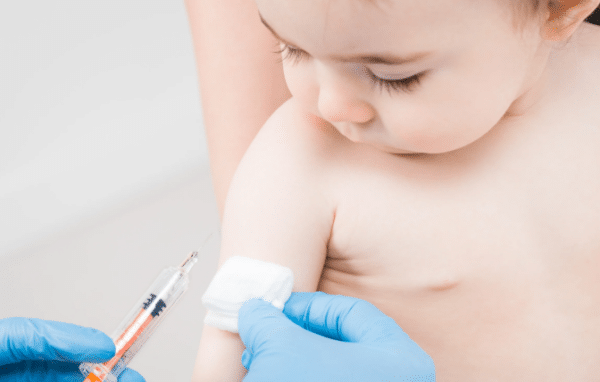

2026 Childhood Vaccines: Every Shot by Age

Vaccines are one of the best ways to protect kids from serious illnesses. Following a recommended schedule helps children stay… Read More »

Child Vaccine Schedule 2025: What Parents Must Know

As a parent, you want to keep your child healthy and safe. One of the best ways to do this… Read More »